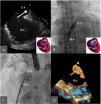

Figure 2.

Cribriform patent foramen ovale occluder embolization and extraction with final implant of the atrial septal defect (ASD) device. A: Transesophageal echography image where the device can be visualized with free movement at the left atrium. B: Device capture at the descending aorta. C: Device extraction through the right femoral artery. D: Final implant of the ASD device.

After release, the device was embolized into the left atrium and descending aorta. The right femoral artery was then canalized and the device was captured with a 30 mm gooseneck snare and externalized through the femoral artery. TEE was then performed under superficial sedation, showing an atrial septal aneurysm, with a wide PFO, and a large membrane distance generating an effective orifice of 18-20 mm. Finally, a 24 mm Amplatzer Septal Occluder (AGA Medical Corporation, Golden Valley, MN, USA) was implanted. Absence of shunt was confirmed via angiography and TTE before delivery (Figure 2). The procedure was concluded successfully and the patient was discharged the following day and prescribed treatment with 100 mg aspirin and 75 mg clopidogrel. In the following weeks there was a progressive improvement in his oxygen saturation, maintaining baseline levels over 90% and he was able to manage without domiciliary oxygen therapy.